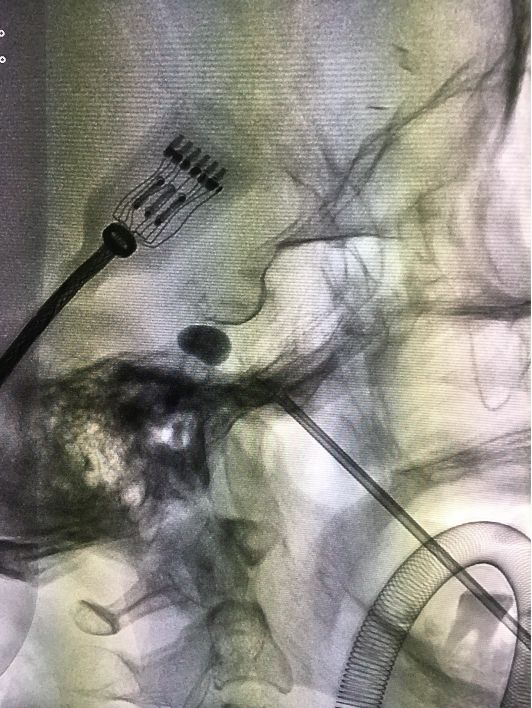

这个手术的核心武器就在于一根15厘米长的套管针,手术时要全麻,在神经介入导管室进行,医生从她左嘴角边上2.5厘米的地方将针穿进,通过神经介入DSA设备多角度透视定位,安全引导套管针到达颅内三叉神经根部,然后将针芯抽出,采用神经介入导管操作技术把跟水笔笔头差不多大的球囊通过管道塞到根部,向球囊注射造影剂扩张,持续压迫神经5分钟,使神经发生变化,传导受限,达到治疗效果。